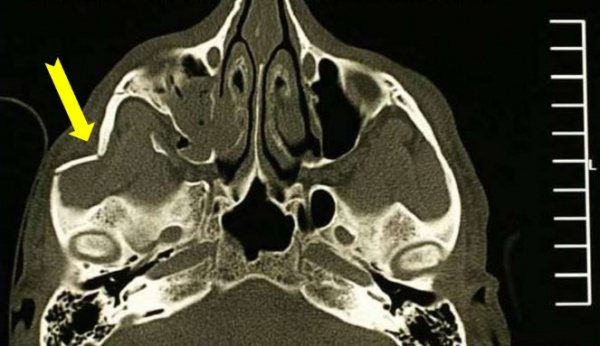

• КТ скуловой кости. Он используется при сложных множественных переломах, которые одновременно повреждают близлежащие кости. Обеспечивает точное определение степени тяжести травмы и расположения отломков.

Компьютерная томография. Перелом скуловой дуги (желтая стрелка).